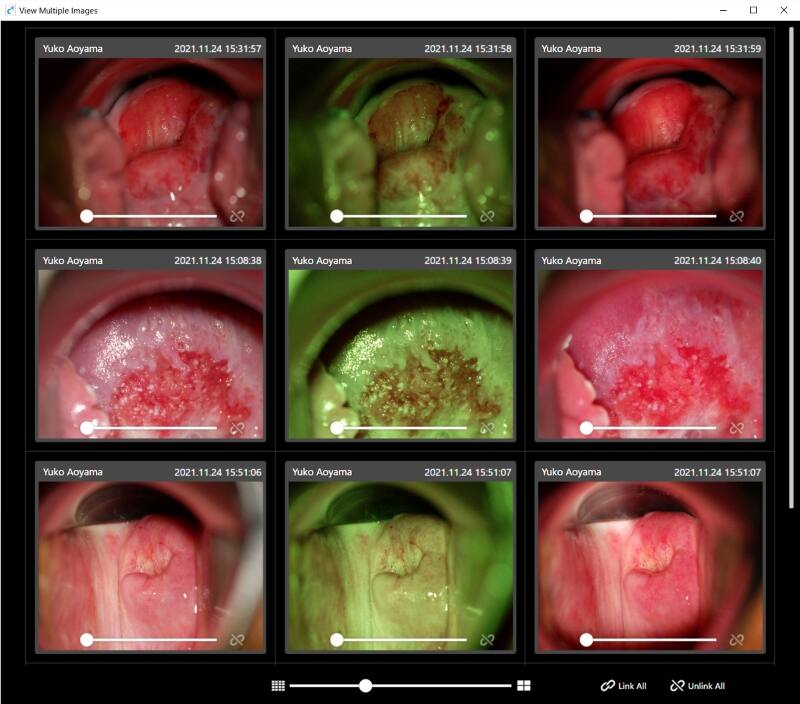

Displaying multiple images

Multiple selected images can be displayed in the same screen.

The same lesions can be compared in chronological order, or similar lesions can be viewed and compared side by side.